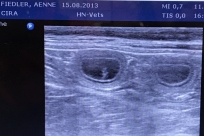

Am Tag 25 nach dem Decken waren wir beim Ultraschall….und wir haben gleich ein paar kleine Embryonen gesehen, die mal zu kleinen Dalmatinerbabys heranwachsen werden – jippi …Cira bekommt Babys 🙂